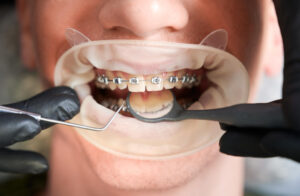

Una sonrisa alineada transmite salud y confianza. Aun así, muchas personas conviven con dientes chuecos, una condición que puede afectar la estética y la función

Una sonrisa alineada y saludable es un reflejo de bienestar y confianza. No obstante, alcanzar ese resultado requiere un proceso ortodóntico cuidadoso seguido, inevitablemente, por